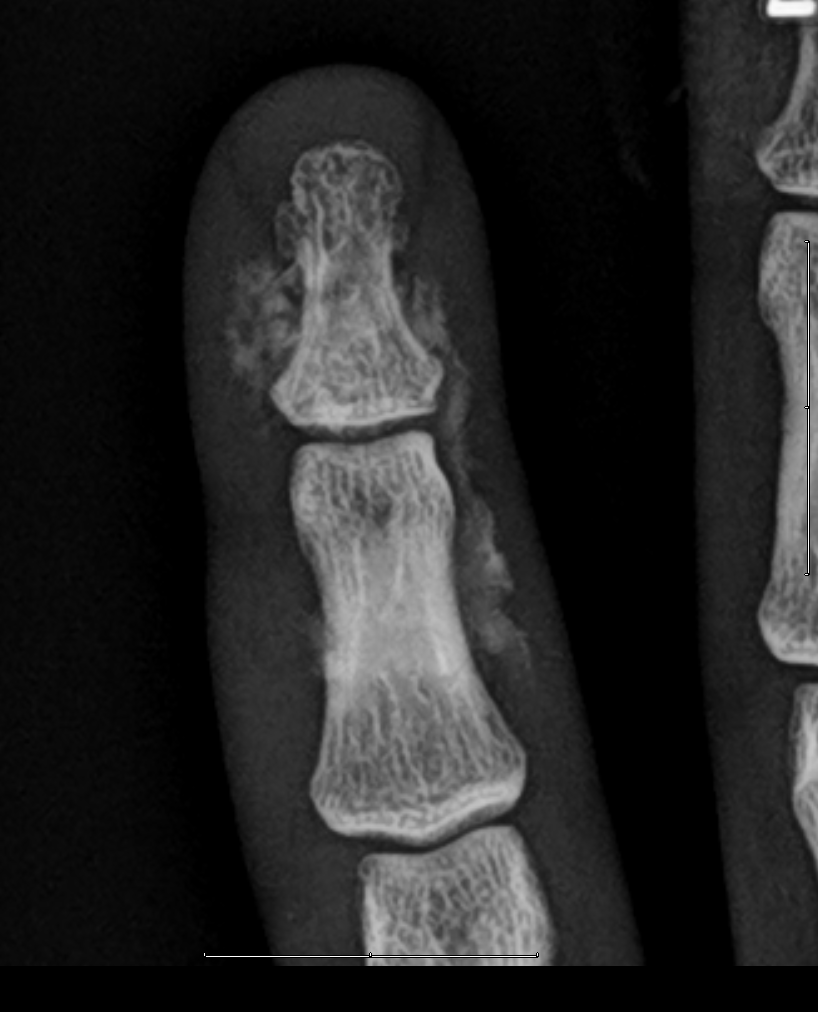

High-pressure soft tissue injuries with a characteristic small entry wound, which can clinically mask the extent of the injury. Radiographs show the extent of the radiopaque paint, but upon surgery, the soft tissue injury is usually even wider (see attached paper), as suggested here by the soft tissue edema. The cases in the attached paper are rather similar to this one and had good outcomes with prompt surgical debridement.